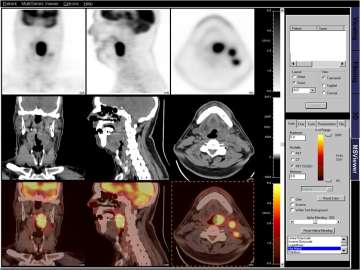

A PET/CT simulation is often but not always used for cancers of the head and neck, cancers of the lung, cancers of the gastrointestinal tract, cancers involving the lymphatic system, as well as other cancers (Figure 1). There is compelling recent scientific evidence that using a PET/CT scan to plan radiation leads to improved tumor control and outcomes for patients. In collaboration with the Division of Nuclear Medicine at UCLA, we are leaders in the advancement of functional imaging such as PET imaging in improving outcomes in radiation treatments for cancer. Current projects include better ways of integrating PET in radiation treatment planning, as well as the use of new tracers in detecting cancer at an earlier stage. We believe that this will make them more amenable to treatment.

Figure 1: The images below represent different imaging modalities used by radiation oncologists to create a more personalized and informed treatment plan.